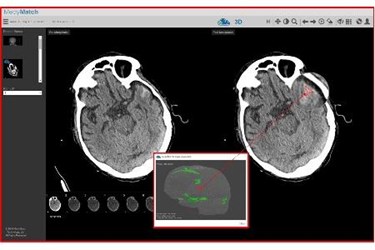

MedyMatch Technology recently announced a collaboration with IBM Watson Health to bring MedyMatch’s A.I.-based clinical decision support application to imaging experts working in hospital emergency rooms and other acute care settings to help doctors identify instances of intracranial bleeding as a result of head trauma and stroke. Initially, IBM Watson Health’s Imaging group will distribute the MedyMatch brain bleed detection application globally through its vendor neutral sales channels. Moving forward, IBM Watson Health and MedyMatch will develop interoperability between MedyMatch’s application and IBM Watson Health Imaging’s offerings.

MedyMatch aims to bring cognitive tools into the daily workflow of an emergency department to help physicians assess patients suspected of head trauma or stroke, and rule out the presence of a bleed in the brain. The MedyMatch algorithm uses sophisticated deep learning, machine vision, patient data, and clinical insights to automatically highlight for a physician regions of interest that could indicate the potential presence of cerebral bleeds –and does so without interrupting how a physician works.